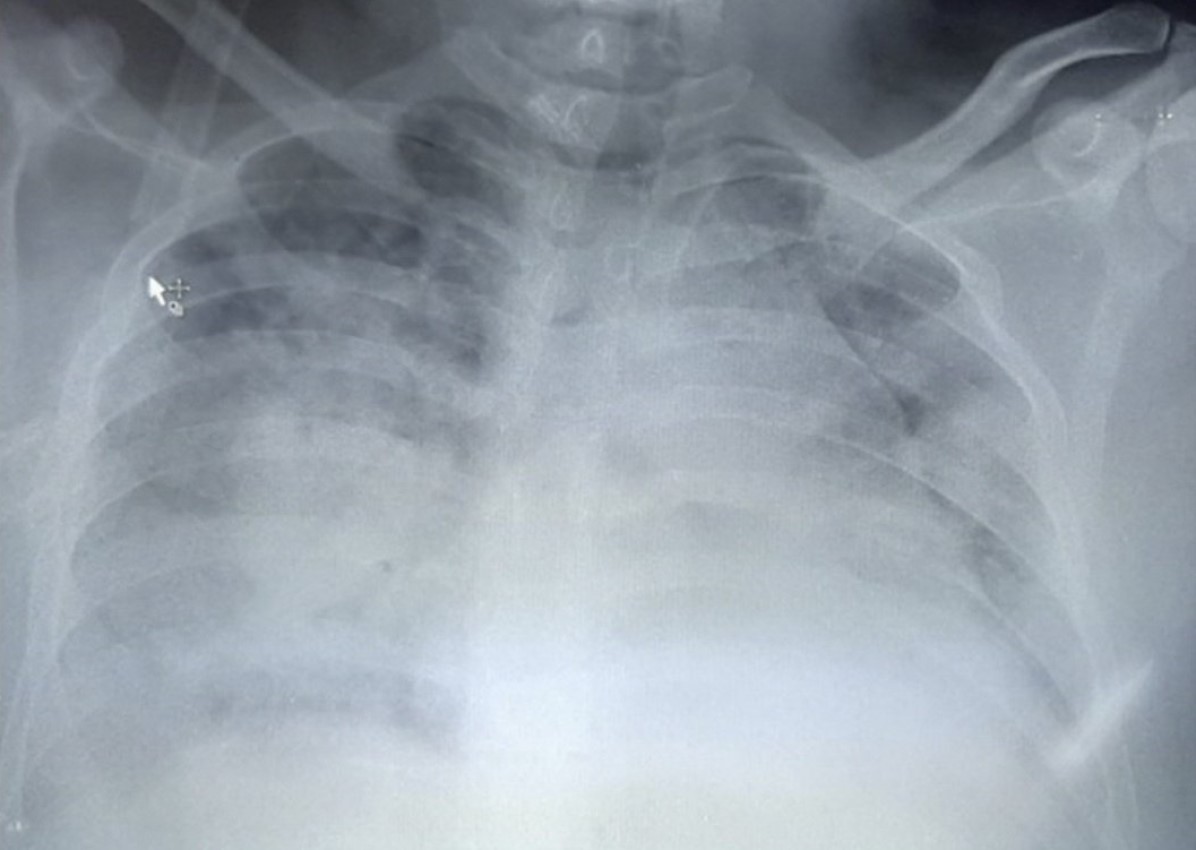

Kako zaraza utiče na čovjeka: Hirurg objavio snimak pluća pacijenta koji je umro od posljedica korone FOTO

07.10.2020. | 13:00Hirurg iz Kragujevca doktor Vladimir Đurić ponovo je na Tviteru objavio snimak pluća svog pacijenta koji je preminuo od posljedica teške upale pluća izazvane korona virusom.